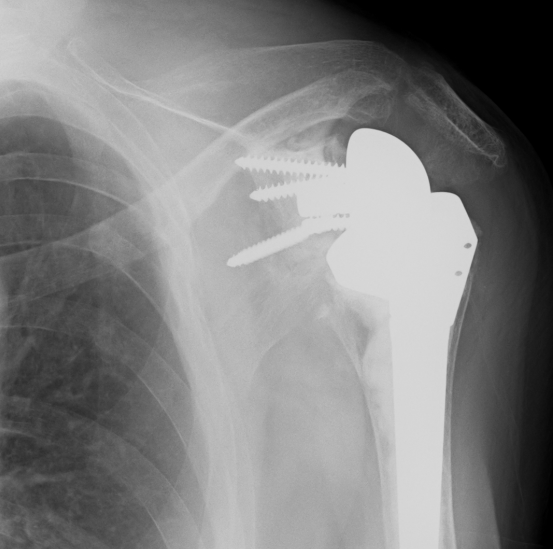

Periprosthetic fracture

Reverse TSR NotchingGlenoid fracture

Stable humeral component treated with ORIF

hum #Hum #Hum #

Unstable humeral component